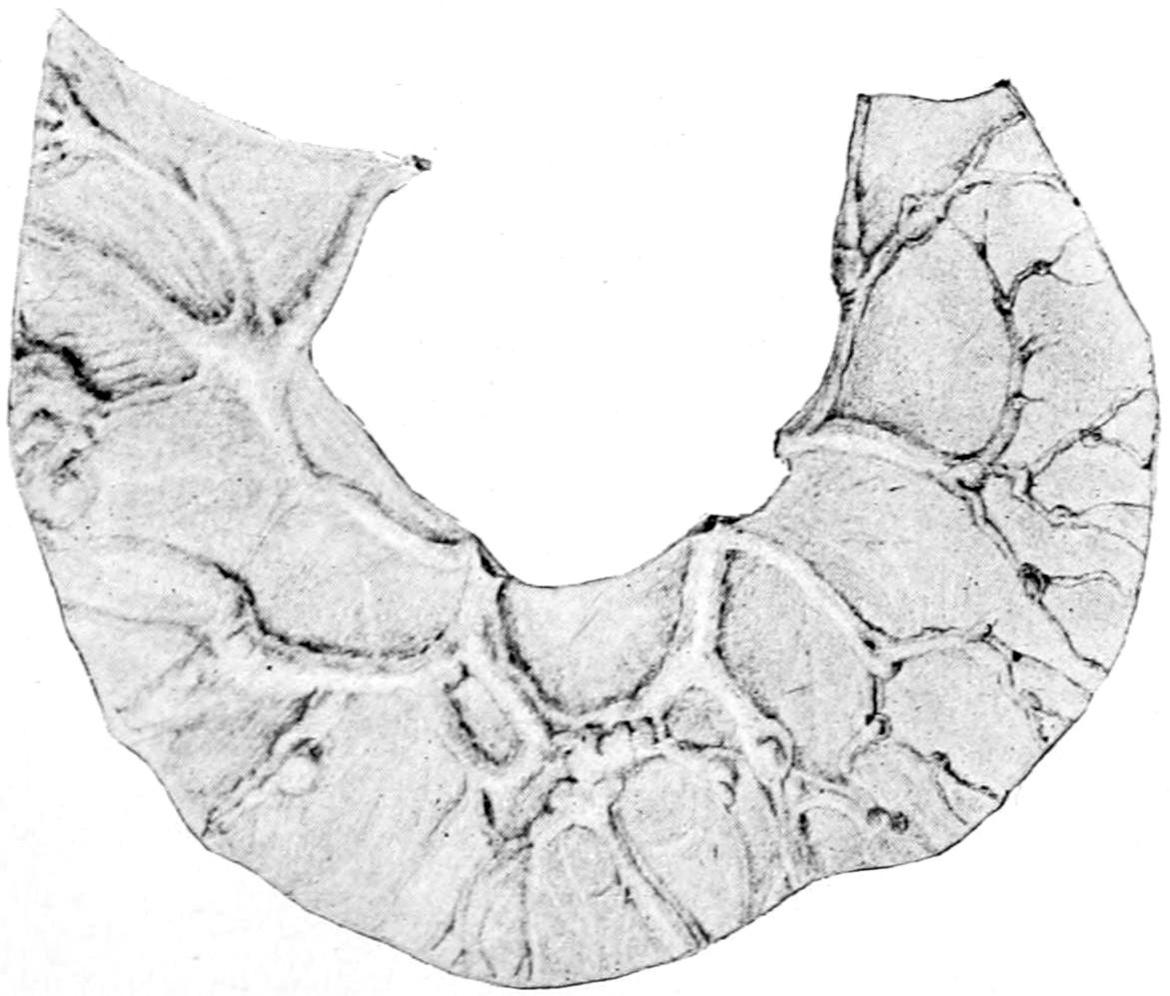

SURGICAL DISEASES OF THE OSSEOUS SYSTEM 416

CHAPTER XXXIII.

DEFORMITIES DUE TO CONGENITAL DEFECTS OR ACQUIRED DISEASES OF THE LOCOMOTOR APPARATUS; ORTHOPEDICS 444

CHAPTER XXXIV.

FRACTURES 479

CHAPTER XXXV.